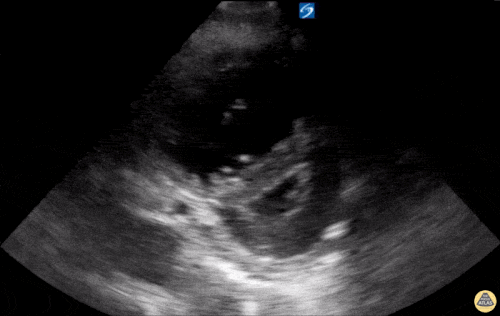

3

Based on the ultrasound image above, which shock etiology is most likely?

1 pts